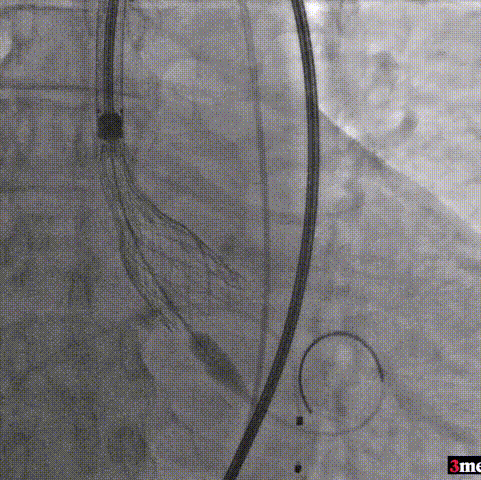

手术过程回顾:

患者全麻后,右侧股动脉建立主入路,主动脉根部造影显示主动脉瓣明显钙化。心室内轻微反流,主动脉及心脏情况整体较为稳定。直头导丝跨瓣后,在超硬导丝支撑下,瓣膜输送系统顺利跨瓣。在180次/分快速心室起搏下,确定降压至50mmHg后选择25mm球囊进行预扩张。根据术前评估及球囊预扩情况,最终选择直径29mm瓣膜进行植入。

主动脉根部造影

直头导丝跨瓣

球囊预扩

输送器过弓

输送器定位

瓣膜脱钩